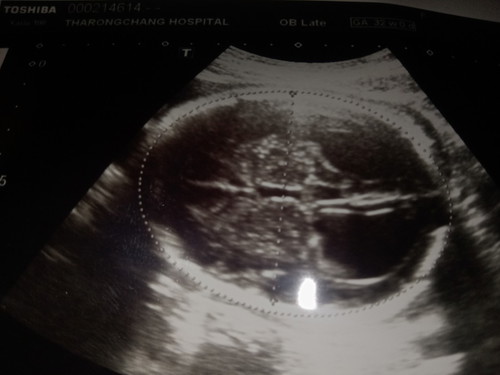

ลูกน้ำในสมองไม่เท่ากัน

ขอสอบถามแม่ๆนะคะ ตอนนี้ 33 w +1d หมอตรวจพบว่าน้ำในสมองของเด็กทั้งสองข้างไม่เท่ากัน จะเป็นอันตรายอะไรมั้ยคะตอนคลอดออกมา ลูกจะมีภาวะผิดปกติมั้ยคะ ##ขอบคุณสำหรับคำตอบค่ะ ##ขอบคุณล่วงหน้านะคะ #ท้องแรกคะ #ขอคำแนะนำหน่อยค่ะ #คุณแม่ๆช่วยแนะนำหน่อยค่ะ